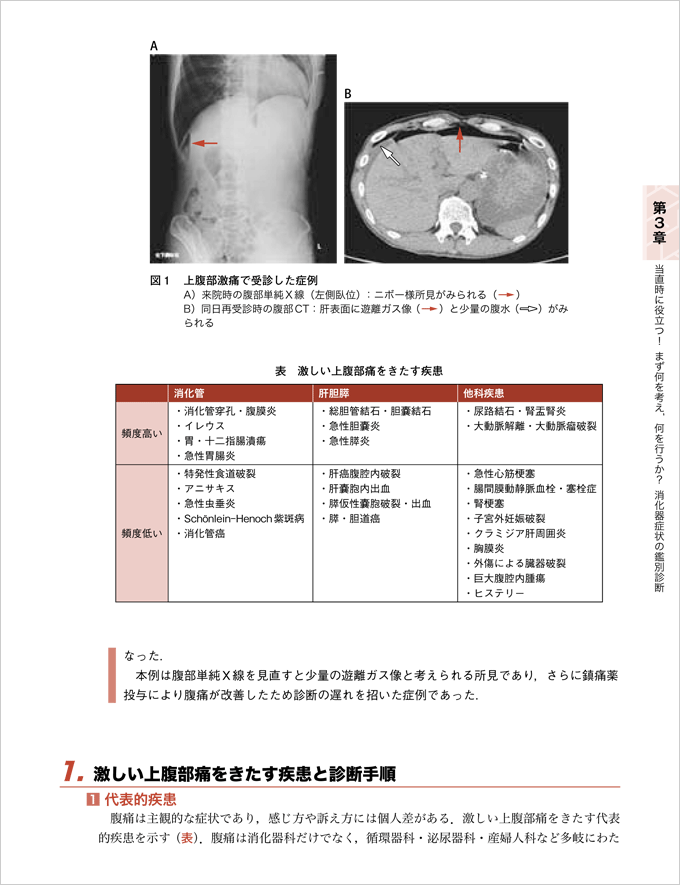

『1. 激しい上腹部痛を訴えて救急来院.鑑別診断,画像診断(CT)の進め方,他科疾患との鑑別のポイントは?』より抜粋

1.激しい上腹部痛を訴えて救急来院.鑑別診断,画像診断(CT)の進め方,他科疾患との鑑別のポイントは?【長谷部 修】